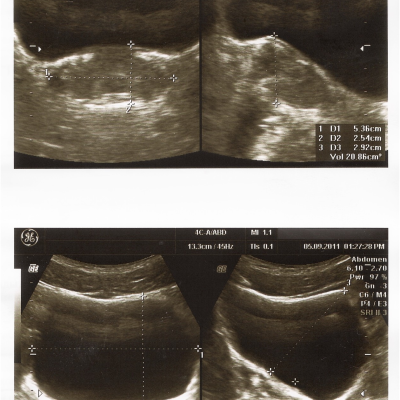

Сходил на прием к урологу, по крови и моче он сказал все в норме, а по узи — простатит. Назначил не дешевое лечение.

Анализы и узи в прикрепленных файлах.